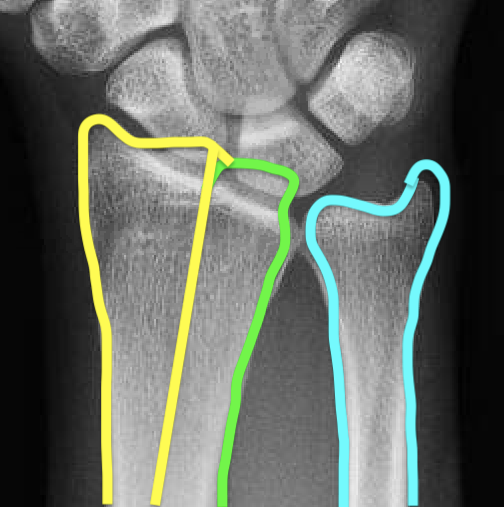

| 3 columns | Three articular surfaces |

Radial column with scaphoid fossa and radial styloid

Intermediate column with lunate fossa and sigmoid notch

Ulna column with TFCC and distal ulna |

Scaphoid facet

Lunate facet

Sigmoid notch |

Radial angles

| Volar tilt mean 11° | Radial inclination mean 22° | Radius mean 11 mm longer than ulna |